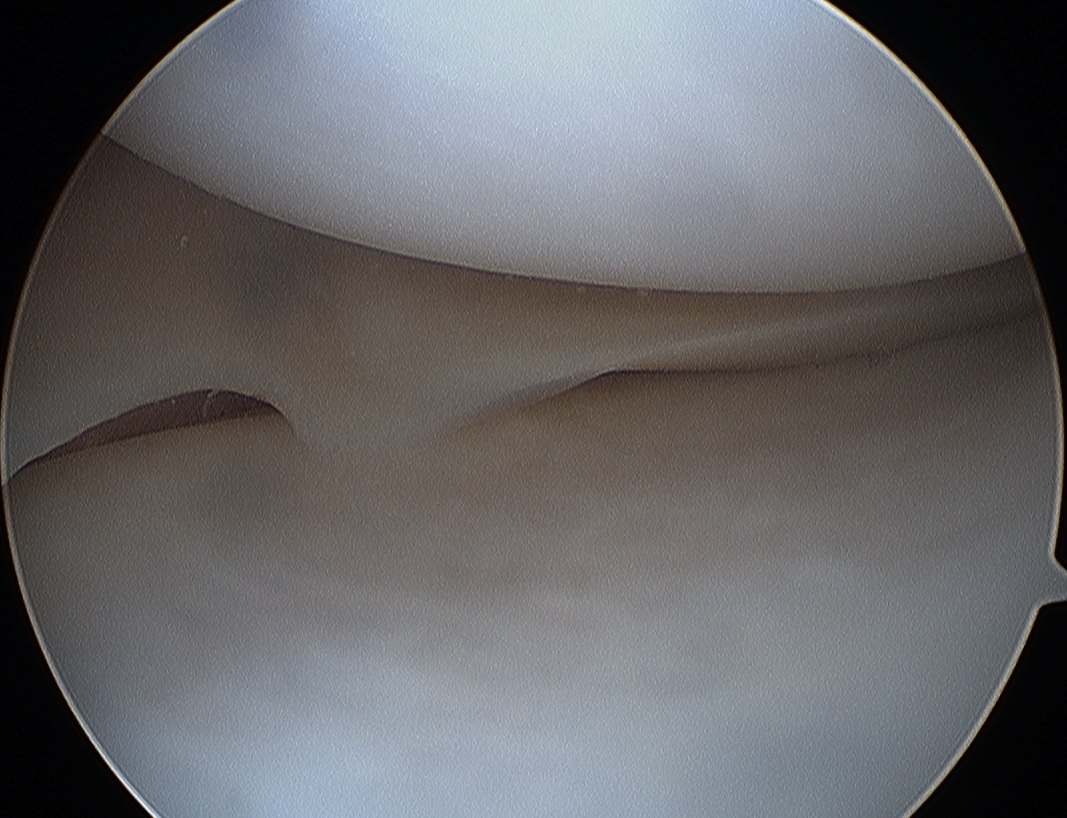

1. Longitudinal Tears

Most common

- vertically oriented tear parallel to edge of meniscus

- usually of posterior part of meniscus

- may occur in either meniscus

- extent varies

A. Incomplete

- usually inferior surface

- may have been complete then healed

- very common posterior horn lateral meniscus after ACL rupture

B. Complete

C. Bucket handle

- displaces into intercondylar notch

- may be central or peripheral

- cause of locked knee

- can damage chondral surface over time